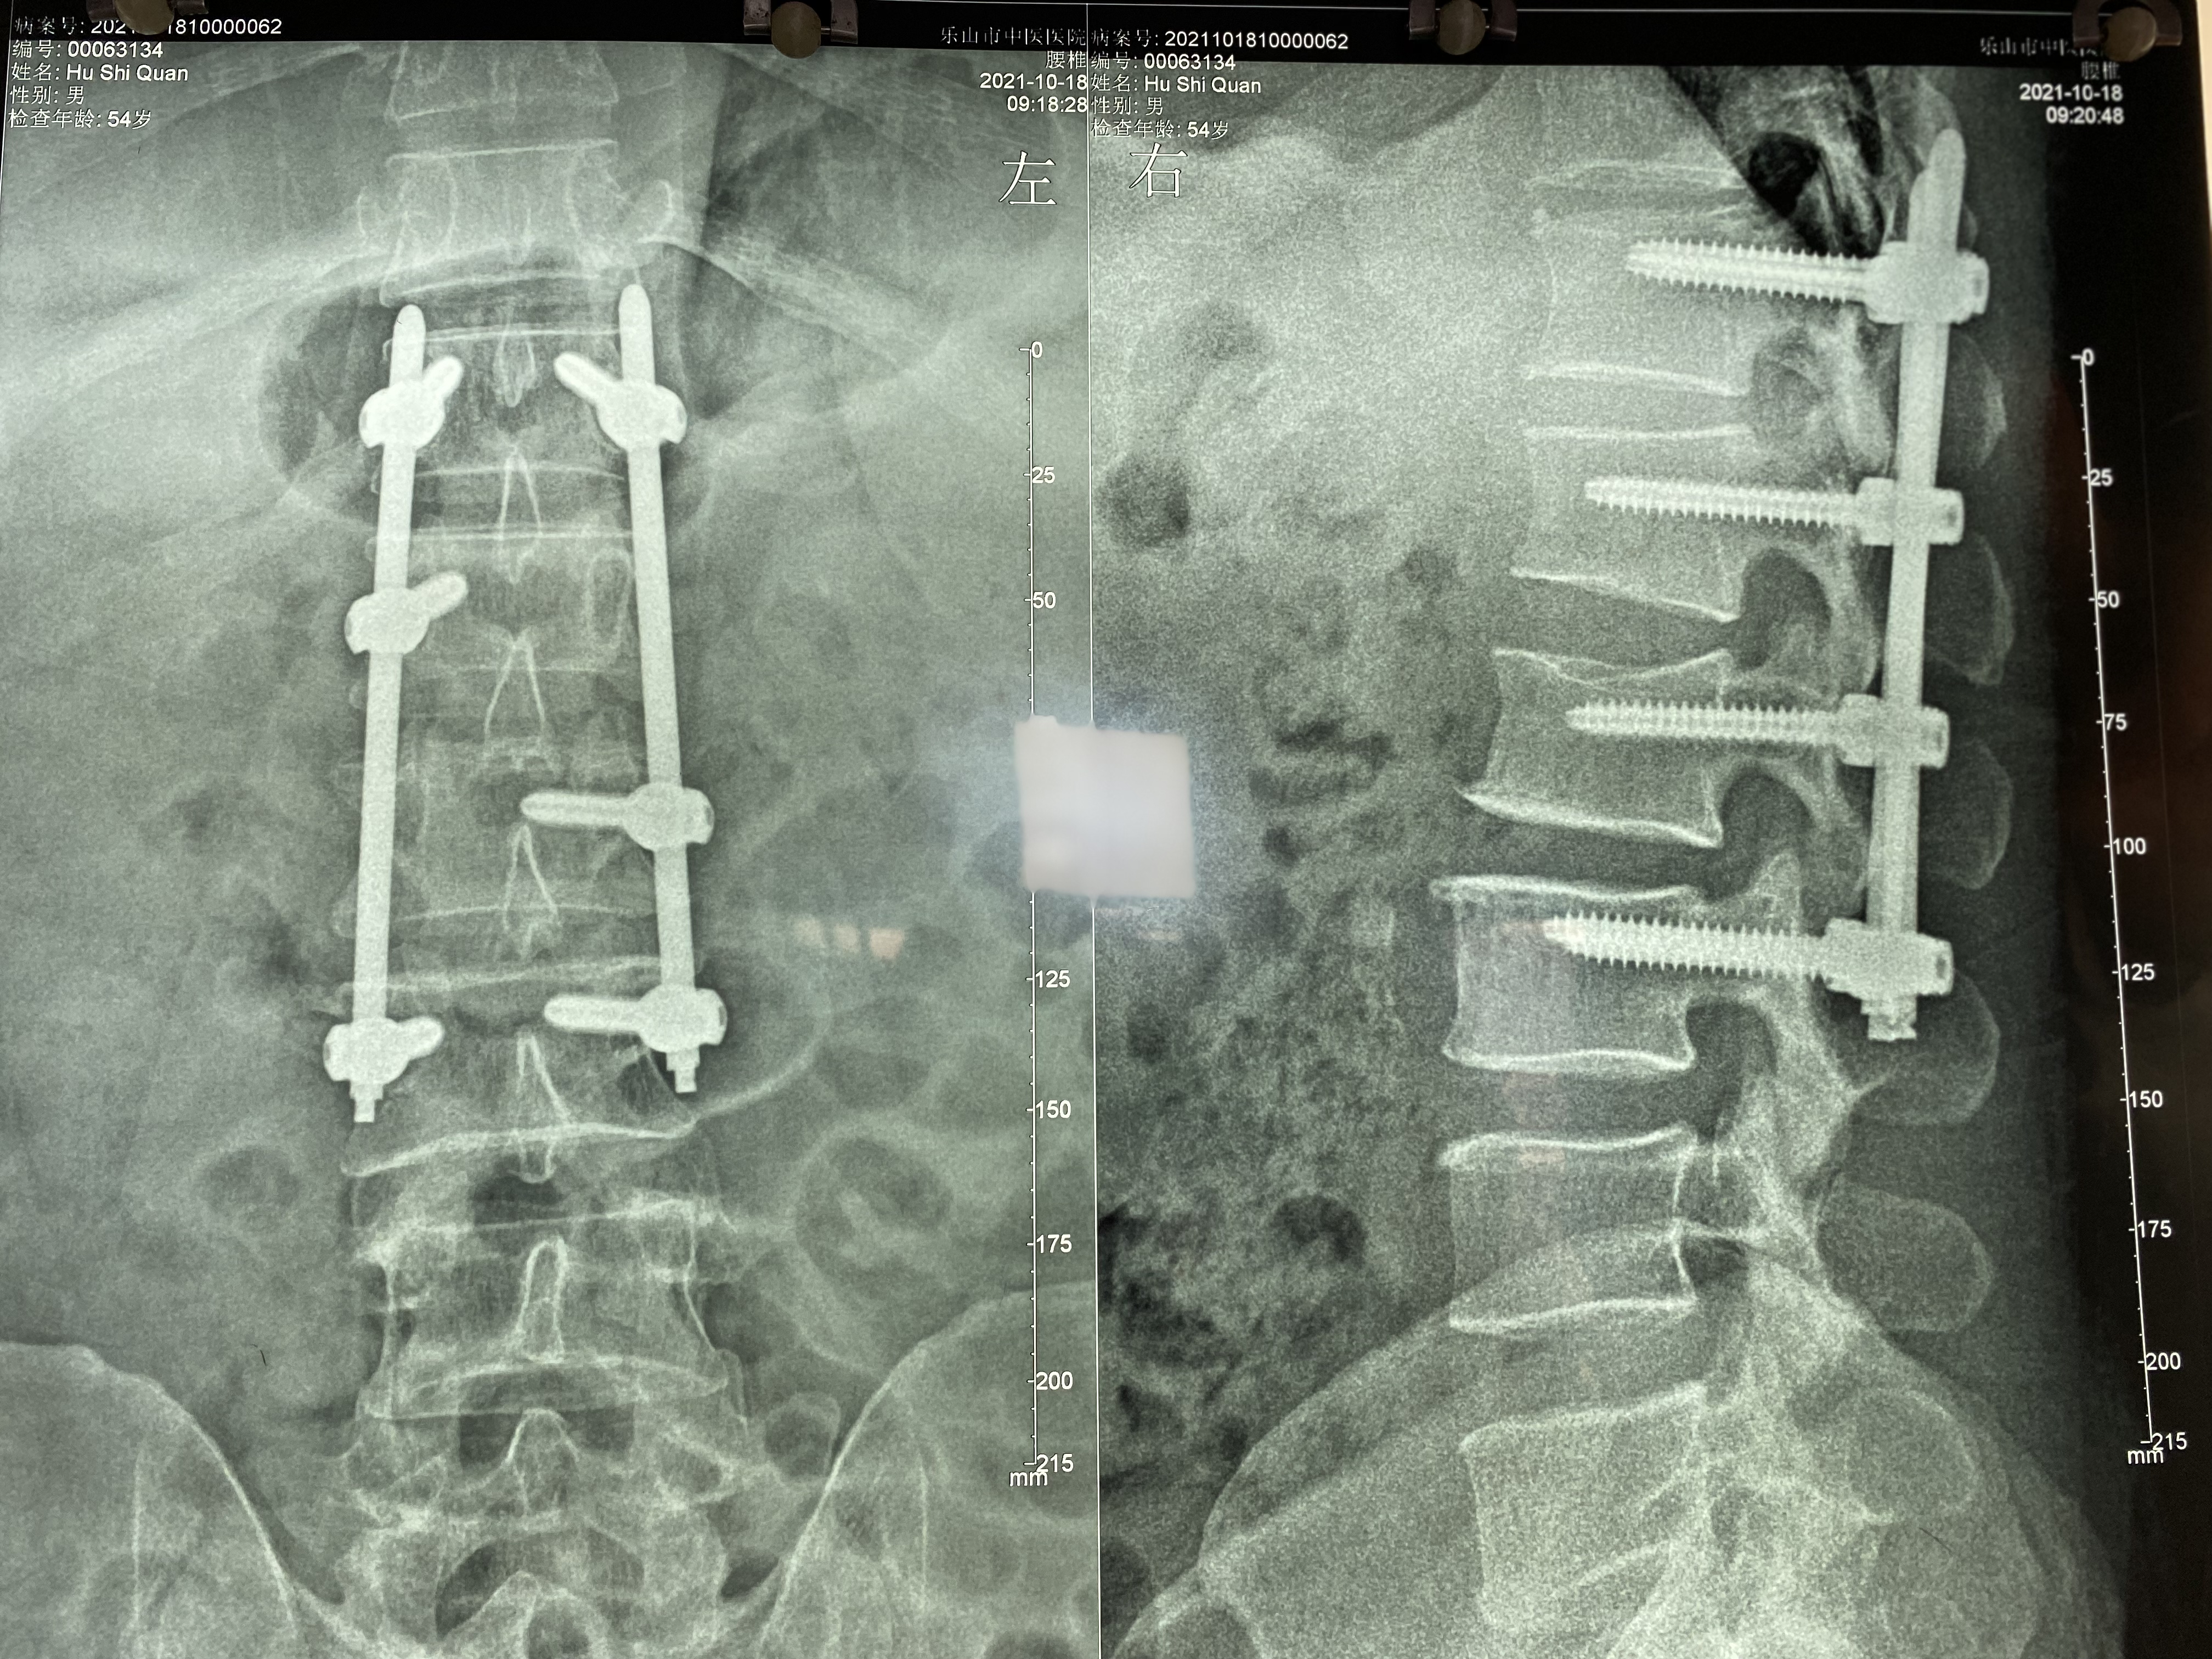

日前,今年 54 岁的胡先生因在工作时,不慎从 3 米高的高凳上摔至地面,其臀部后仰着地致腰 1、2、3 椎外伤性骨折。据了解,事发后,胡先生被 120 救护车送市中医医院急诊科,由于伤势过重而转入骨伤科治疗。

术中,6 个螺钉和 2 个钉棒不偏不倚地固定在胡先生骨折处,其脊柱的序列、高度得以恢复、脊柱的稳定性得以重建,手术花费 1 个半小时,出血量仅为 50 ml。

术后三天,在支具辅助下,能下床行走活动的胡先生露出了满意的笑容。「由于手术切口小,创伤小、术后疼痛轻微,且未破坏脊柱后方韧带、肌肉等结构,所以患者术后恢复快。」高霖介绍到,患者目前处于加强下肢功能锻炼阶段。